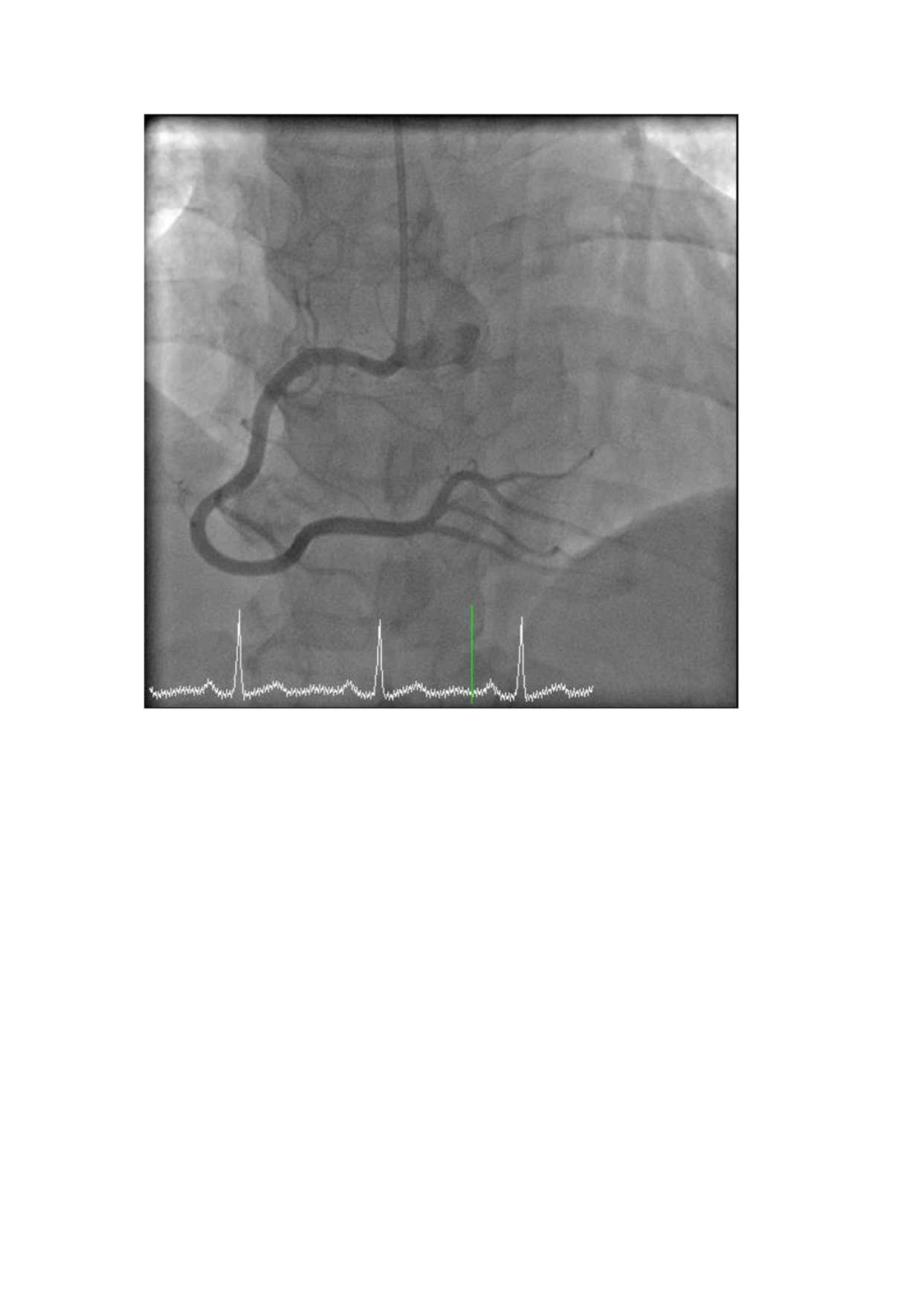

4.辅检:2019. 08.48小时主治医师诊断:史摘要:1.患者,女,57岁;2 .主诉:发作性胸痛胸闷2月,再发1天;3 .查体:神清、气平,全身皮肤未见黄染,全身浅表淋巴结未及肿大。双侧瞳孔等大等圆,对光反射存在。口唇无绢,伸舌居中,颈软,气管居中,颈静脉无怒张,双侧呼吸音清,双肺未闻及干湿罗音。心率70次/分,律齐,未闻及病理性杂音,血压120/8OmmHg。腹软,无压痛、无反跳痛。肝脾肋下未及。双下无肢浮肿。正常生理反射存在,病理反射未引出。02心电图:1.窦性心律;V2-V4导联ST段近似弓背向上抬高0.5mm。不稳定性心绞痛冠心病高血压3级(很高危)WAV郴郴郴郴M产2如郴郴郴l崛八郴蜘郴脾柚腑榔抑曲岫V